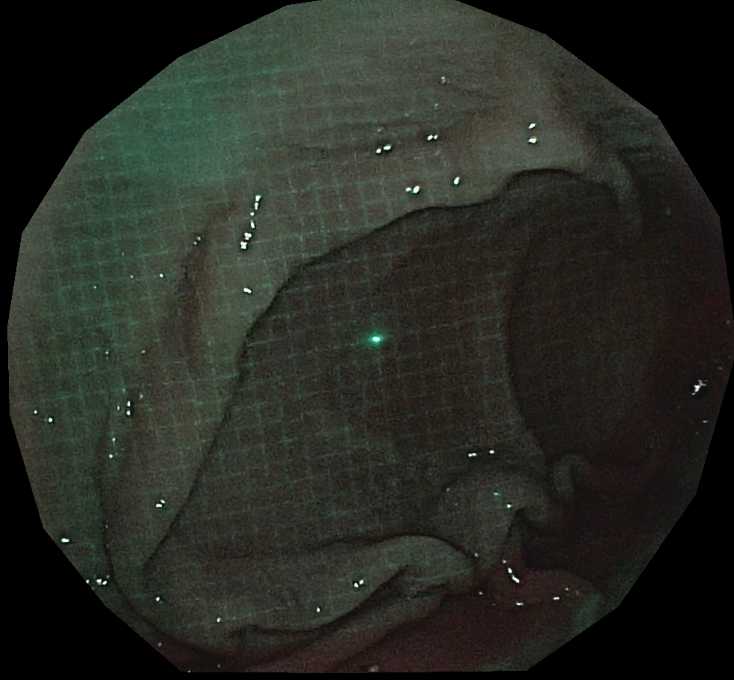

内視鏡の鉗子チャネルに小型パターンプロジェクタを挿入し,

観察対象にパターン光を照射した状態で内視鏡カメラで画像を撮影します.

計測対象は生体組織であるため,組織内の散乱(subsurface scattering)によって投影パターンがぼやけることがあります.

また,内視鏡環境ではノイズや外乱の影響が通常のカメラ環境よりも大きくなります.

これらに対処するため,グリッドパターンのグリッド点をグリッド辺間のギャップで変調するギャップ符号化グリッドパターンと,

DOE(回折光学素子)を用いてシャープにパターンを投影できる超小型パターンプロジェクタを開発しました.

本プロジェクタは画角約90度の広角投影が可能であり,広範囲をカバーできます.

プロジェクタを鉗子孔に挿入することで,

パターンを投影しながら内視鏡撮影を行うことができます.